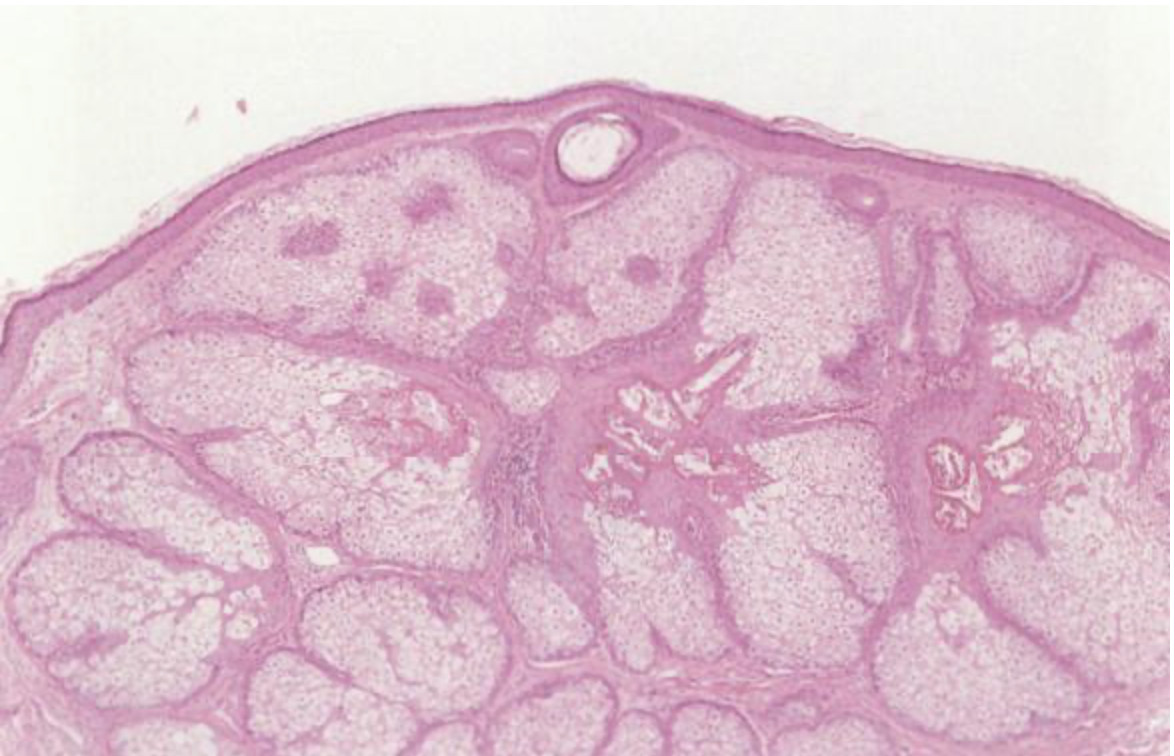

老人性脂腺増殖症の病理像

直径3〜8mm程度の黄白色の丘疹で、成熟した脂腺(皮脂をつくるところ)が増殖して隆起した良性腫瘍です。

中心部が凹んでおり(中心陥凹)、しばしば多発することもあり、皮脂が多い方によくできます。